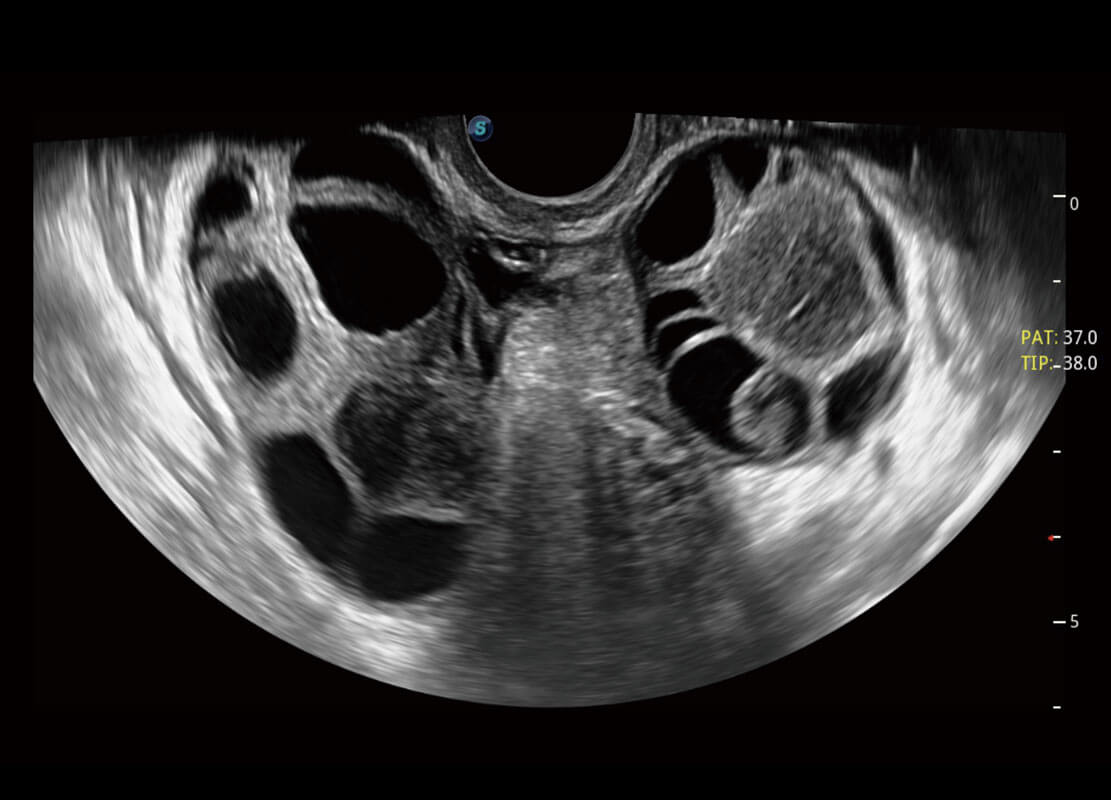

P60優(yōu)異的圖像質(zhì)量搭載專科探頭,在婦科基礎(chǔ)疾病的診斷、卵泡生長(zhǎng)的監(jiān)測(cè)、輸卵管通暢情況的判別等方面為您提供生殖應(yīng)用方案。

腔內(nèi)婦科-卵巢